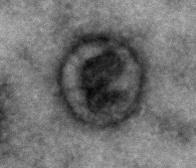

image: In this study, exosomes were isolated from patient-derived cardiospheres and visualized using transmission electron microscopy.

Another important finding was the mechanism through which CDCs actually lead to improved cardiac function. Indeed, their analyses revealed that transplanted cells secrete small vesicles called "exosomes," which are enriched with proteins called "microRNAs" that initiate a whole cascade of molecular interactions. These microRNA-enriched exosomes have two effects. First, it blocks the damage-inducing cells from causing further harm to the heart tissue. Secondly, it induces the differentiation of stem cells into fully functioning cardiac cells ("cardiomyocytes"), starting the regenerative process. This generates hope that injecting these exosomes alone might be enough to reverse this type of heart damage in patients, bypassing the need for CDCs in the first place.